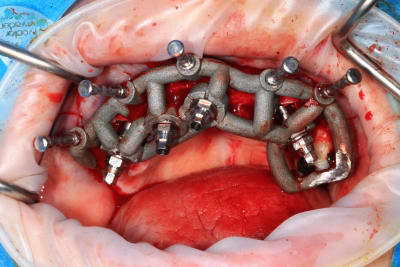

Le cas N°2 en images reelles :)

Guide métal avec support clavette, os assez fin : il est prévu un sticky bone complet : donc : lambeau avant extraction, positionnement du guide base et forage des clavettes, positionnement du guide implant, pose des piliers MU, controle des axes prothétique avec le guide pilier, collage des piliers prov sur le bridge a armature métal, occlusion nickel, sticky bone et PRF, sutures suspendues.

T’as quand même une sacrée déviation des implants / à la planification…..

Ça se voit déjà avec les implants posés à travers le guide de forage métallique qui est amha trop permissif

Et c’est confirmé par ton guide pour les piliers multiunits qui n’est même pas à fond (clavette antérieur pas mise….enfin certainement impossible à mettre)

Mais tu as raison, il y avait un peu trop de jeu au niveau du guide .

C’est le premier entièrement métallique que je fais imprimer ( Fridentech ). Il faut que je fasse un modèle avec plusieurs diamètres pour avoir le meilleur ajustage . Je pense que le mieux serait d’insérer une douille ETK. C’est ce que fait Dimitri avec ses guides métalliques codiagnostic.

Voilà les photos du cas , avec un peu de retard.

06C757A0-0679-4A5E-A2AD-9E867A3CB080.jpeg

65672A94-F454-46C1-A2A7-47927485B543.jpeg

143DCC8C-EA6F-4EE5-9915-F12A33C377B9.jpeg

F8362BF2-81BC-455C-BFD0-A9FE9451F3F4.jpeg

91CE34AF-EDB6-436D-8B12-726F81FC0CB1.jpeg

4060EC60-1F78-4778-B0E3-5FE470671FDF.jpeg

F4ECCBAA-30DE-407C-AAD1-02D226210CC9.jpeg

C4C89A41-3628-4190-A864-AFFC591089BF.jpeg